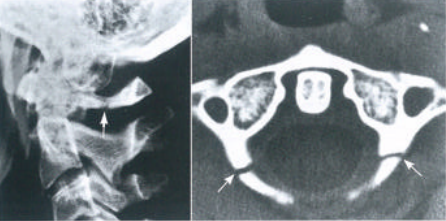

齿状突骨折Anderson和D' Alonzo将齿状突骨折分为3型(图14):Ⅰ型:齿状突尖骨折齿状突尖的斜形骨折,受伤机制可能为剪切外力导致齿状突尖撞击枕骨大孔边缘,也见于寰枕关节脱位时的翼状韧带撕脱骨折。Ⅱ型:齿状突骨折骨折线位于齿状突基底,C2椎体上方。骨折接触面小,保守治疗容易出现骨折不愈合。骨折线也可为斜形,此时齿状突可向前或向后移位。Ⅲ型:经枢椎体的齿状突骨折骨折线位于枢椎椎体,齿状突腰部以下。Anderson和D' Alonzo报道此型骨折线位于松质骨内,容易愈合,保守治疗的不愈合率仅为7%。骨折线常进入侧方寰枢关节并导致关节面台阶。

图14 Anderson和D' Alonzo齿状突骨折分类

有时骨折线是不对称的,一侧垂直进入C2/3椎间隙,另一侧骨折线靠近后方而产生类似外伤性椎体滑脱的骨折。